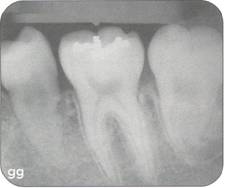

Fi 545e45f g 5-8i Radiographic evaluation of the donor tooth. Several angulations should be used to determine the likely fit of the donor tooth into the recipient site. If the first premolar is double-rooted, consider using the second premolar as a donor tooth. |

|